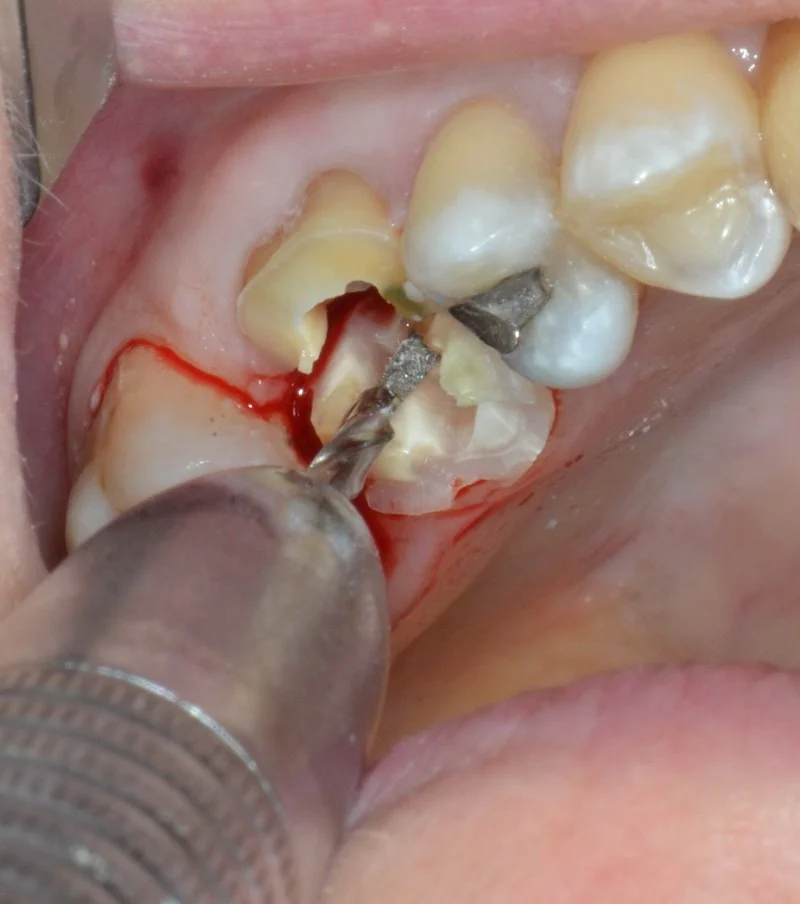

Les extractions simples deviennent rapidement complexes lorsqu’on manque d’outils, de vision ou de stratégie. Cette formation de 3 jours, donnée par un chirurgien maxillo-facial, est conçue pour les dentistes qui veulent passer au niveau supérieur et aborder les cas difficiles avec précision, confiance et maîtrise.

Et pour rendre l’apprentissage encore plus concret, vous pourrez amener jusqu’à deux de vos propres patients et réaliser la chirurgie de votre choix sous supervision directe. Une occasion unique de pratiquer, de progresser rapidement et d’intégrer immédiatement ces compétences à votre réalité clinique.